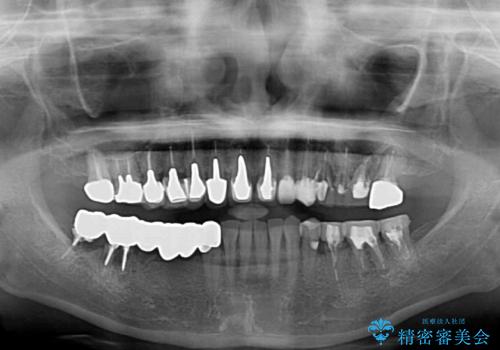

- 以前治療した歯が欠けたり、痛みを感じたりしているとのことで来院された患者様です。

アメリカ国内を転々としながら治療を行ったため治療跡がモザイク様で、クラウンが壊れていたり、抜歯が必要であったりしていました。

上下左右すべての奥歯に処置が必要であり、同時に行うと食事が取りにくくなってしまったり、手前の歯に負担がかかって初診時よりも状況が悪化したりする可能性があるため、片方ずつ処置を進めて行くこととしました。

下顎右側は骨造成を併用してインプラント治療を行い、その他の奥歯もインプラントや歯周外科処置を併用して補綴治療を進め、最後に前歯部の欠けてしまったセラミッククラウンを作り替えることとしました。